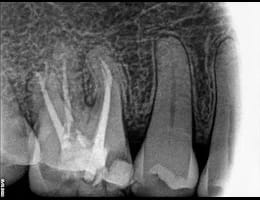

The dentist examines the tooth and takes X-rays to confirm the extent of infection or damage.

DIGITAL X RAY “RVG”

We invest in the latest imaging technologies like Carestream RVG IOPA to provide superior diagnostic capabilities.

Expert Analysis:

Our experienced dental team is skilled in interpreting RVG IOPA images, ensuring that any dental issues are accurately identified and addressed.